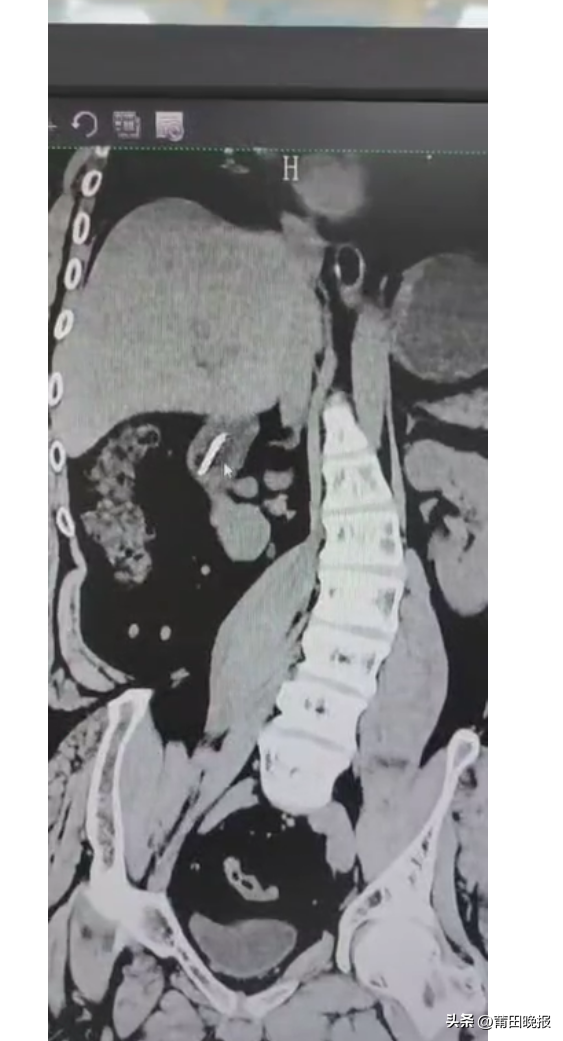

11月4日晚11点左右,22岁的患者傅某已刷好牙,为了进一步清洁舌苔,于是高仰着头刷洗舌根部,一不留神牙刷滑入咽喉部,随之剧烈的干呕,不但吐不出来反而越吞越深,继而不一会儿的功夫把整支牙刷都吞入。此后,患者至市内多家医院就诊,经外院医师推荐于次日10时许至莆田学院附属医院急诊科就诊,行急诊胸腹部CT发现1支长达18 cm牙刷倒置斜插在胃-十二指肠降部,经消化内科、胃肠外科联合会诊,考虑异物长且滞留位置较深,内镜取出难度极大,不排除需要转外科手术取出的可能性。听闻如此,现场患者及家属后悔自责而难过不已。

消化内镜中心值班医生宋聪华博士在了解情况后,再次对患者进行了病史询问和体格检查,在分析患者上消化道内牙刷的形状、滞留的位置及牙刷的轴向与消化道解剖结构的走形关系后,初步判断牙刷未引起消化道出血、梗阻和穿孔等并发症,且仍有内镜下取出牙刷的可能性。